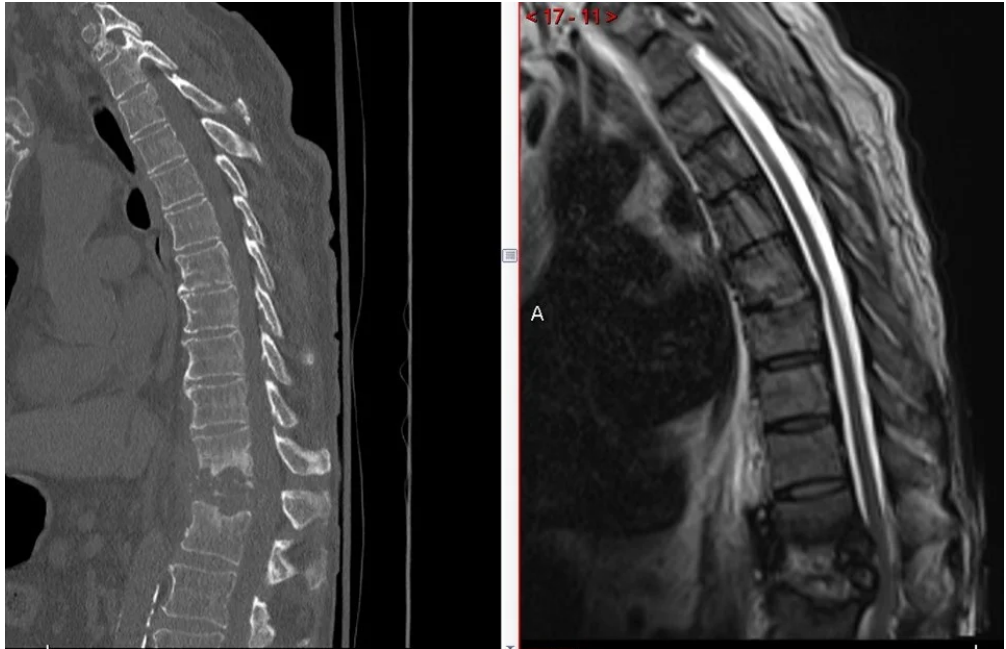

Thoracic Corpectomy